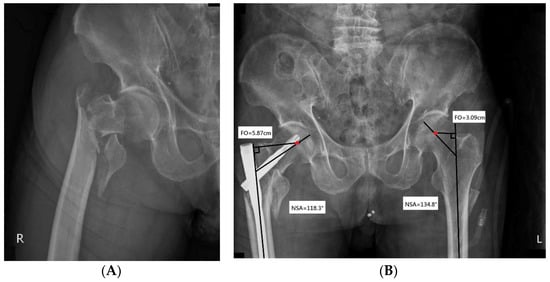

Figure 2.

(A) An 85-year-old woman experienced severe hip pain after a fall. Radiographic examination of the right hip revealed an unstable ITF (type A2.2 according to AO/OTA classification). She underwent open reduction and internal fixation with PFNA-II. (B) Post-operative radiograph shows the wedge effect. The combination of decreased NSA and increased FO was noted upon comparison with the non-injured hip joint. Red dot represents the center of the femoral head.

Each patient underwent an X-ray examination to determine the integrity of the lateral wall. Neck-shaft angle (NSA), FO, and tip-apex distance (TAD) were evaluated on AP radiographs. NSA was defined as the intersection angle between the femoral neck axis and the femoral shaft axis (Figure 2) [16]. A change in NSA was measured by subtracting the NSA of the injured hip from that of the contralateral side. FO was defined as the perpendicular distance from the center of rotation of the femoral head to the long axis of the femoral shaft on AP radiographs (Figure 2) [17]. A change in FO was measured by subtracting the FO of the injured hip from that of the non-injured side. TAD and Parker’s ratio were used to evaluate the blade position. TAD was defined as the sum of the distance from the tip of the helical blade to the apex of the femoral head in AP and lateral views [18]. Parker’s ratio was measured according to the method described by Parker [19]. Using this method, the superior, inferior, anterior, and posterior borders of the femoral head were identified on AP or lateral radiographs. The blade position ratio was calculated by dividing the length from the blade’s center to the inferior border in AP view or posterior border in lateral view by the length of the femoral head in AP or lateral view, respectively.